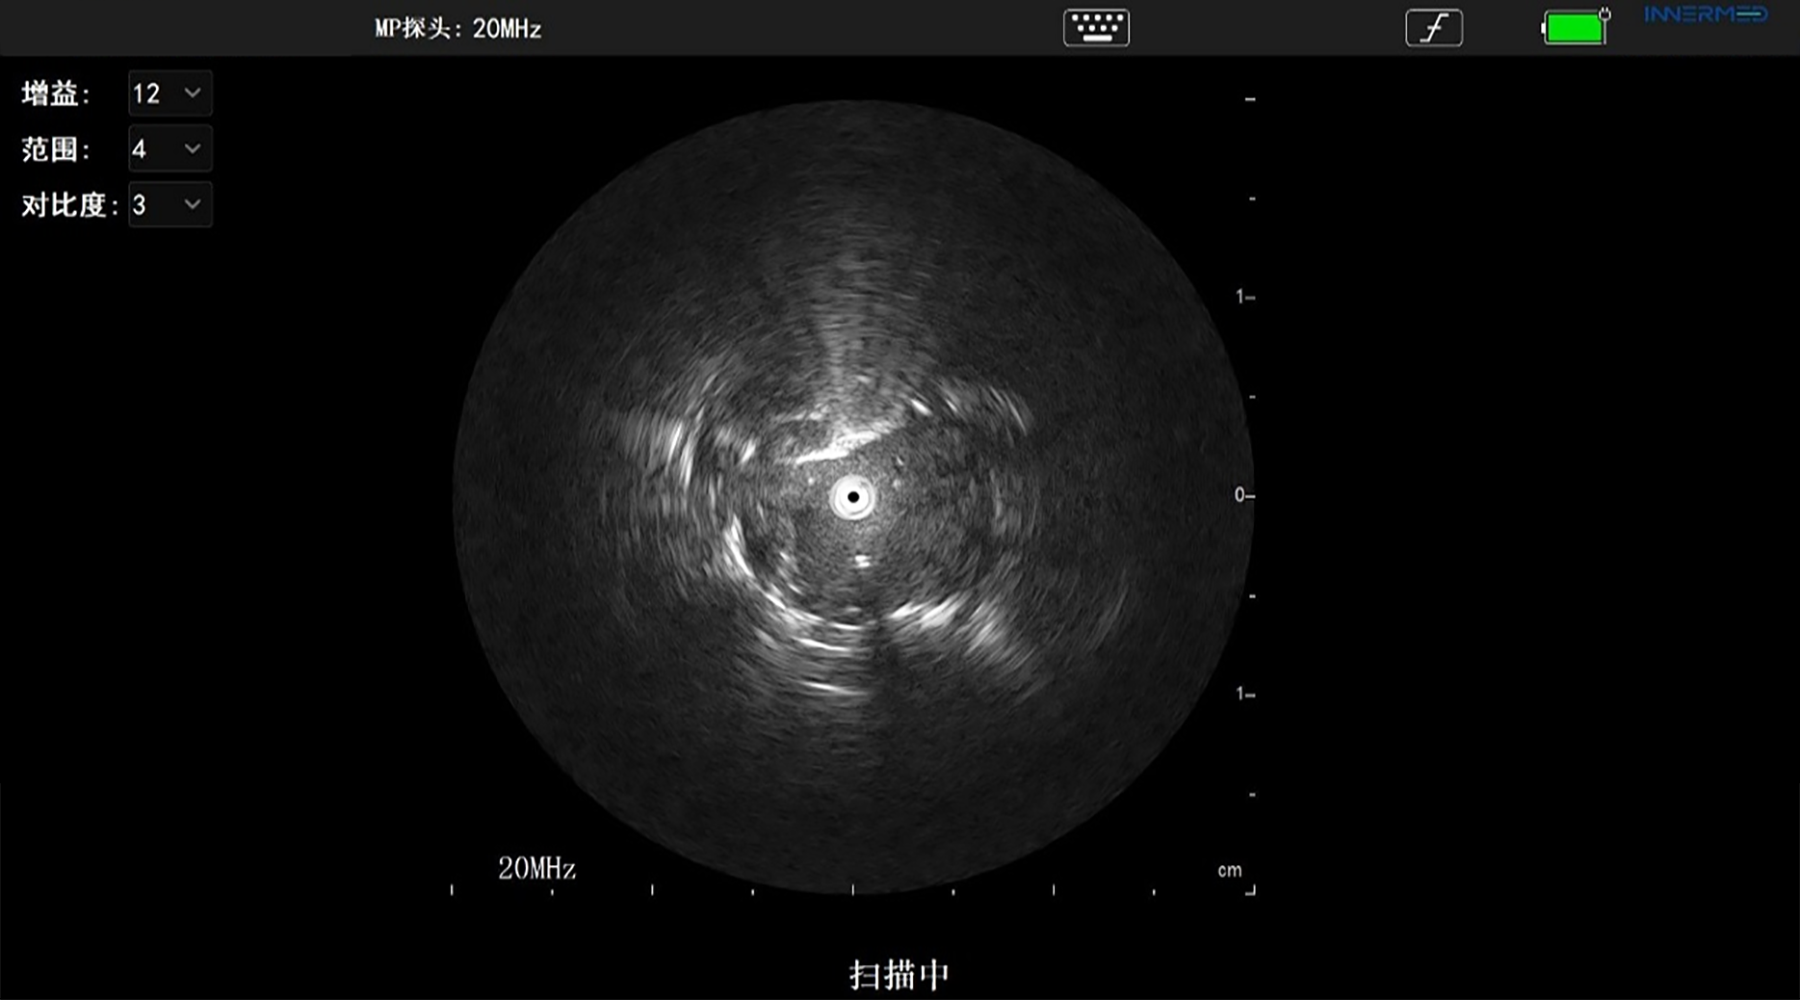

随即医院针对该病例组织多学科协作团队(MDT)制定了科学的诊疗方案,为患者实施 EBUS-GS-TBLB 术,采用手绘导航联合英美达呼吸小探头超声内镜(R-EBUS)进行定位、活检,成功为患者诊断提供了精准依据。

英美达呼吸超声诊断图